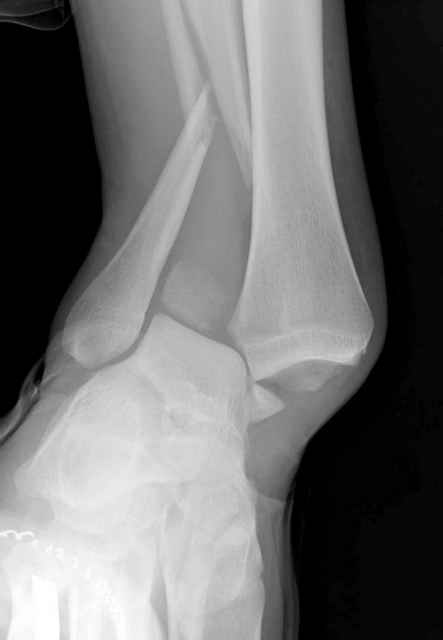

Здесь похожий случай трехнедельной давности, перелом почти сросся и была укорочена малоберцовая, на операции длину малоберцовой смогли восстановить только после того, когда проксимальнее пластины ввели шуруп и использовали его как толкатель, с помощбю дистракционого инструмента (lamina spreader).

Меньше всего волнует положение медиальной лодыжки - в любое время можно провести остео или реостеосинтез, при несращении можно просто резецировать без ущерба для движений в голеностопе. Здесь обошлись фиксацией одним 4 мм канюлированным шурупом.

Конечно, компьютерный томограф более информативный метод, но с помощью недорогого обычного стандартного в нейтральном положении стопы: прямого, бокового и косой (ankle mortise) ренгенологического метода можно получить полную информацию о повреждении голеностопного сустава, а сравнительный снимок с другой стороны подтвердить наличие повреждения.

При реконструкции голеностопа, о важности восстановления длины малоберцовой для профилактики пост травматического артроза разбирали в предыдущих дискуссиях. Нарушенную биомеханику голеностопа без восстановления длины малоберцовой, не восстановить только швом медиальной связки.

Расширенная медиальная щель более чем на 4 мм и укорочение малоберцовой более чем 2 мм, а перелом заднего края большеберцовой смещения более 2мм с вовлечением 30% поверхности сустава, считается отходом от нормы голеностопного сустава, и подлежит к оперативному вмещательству.